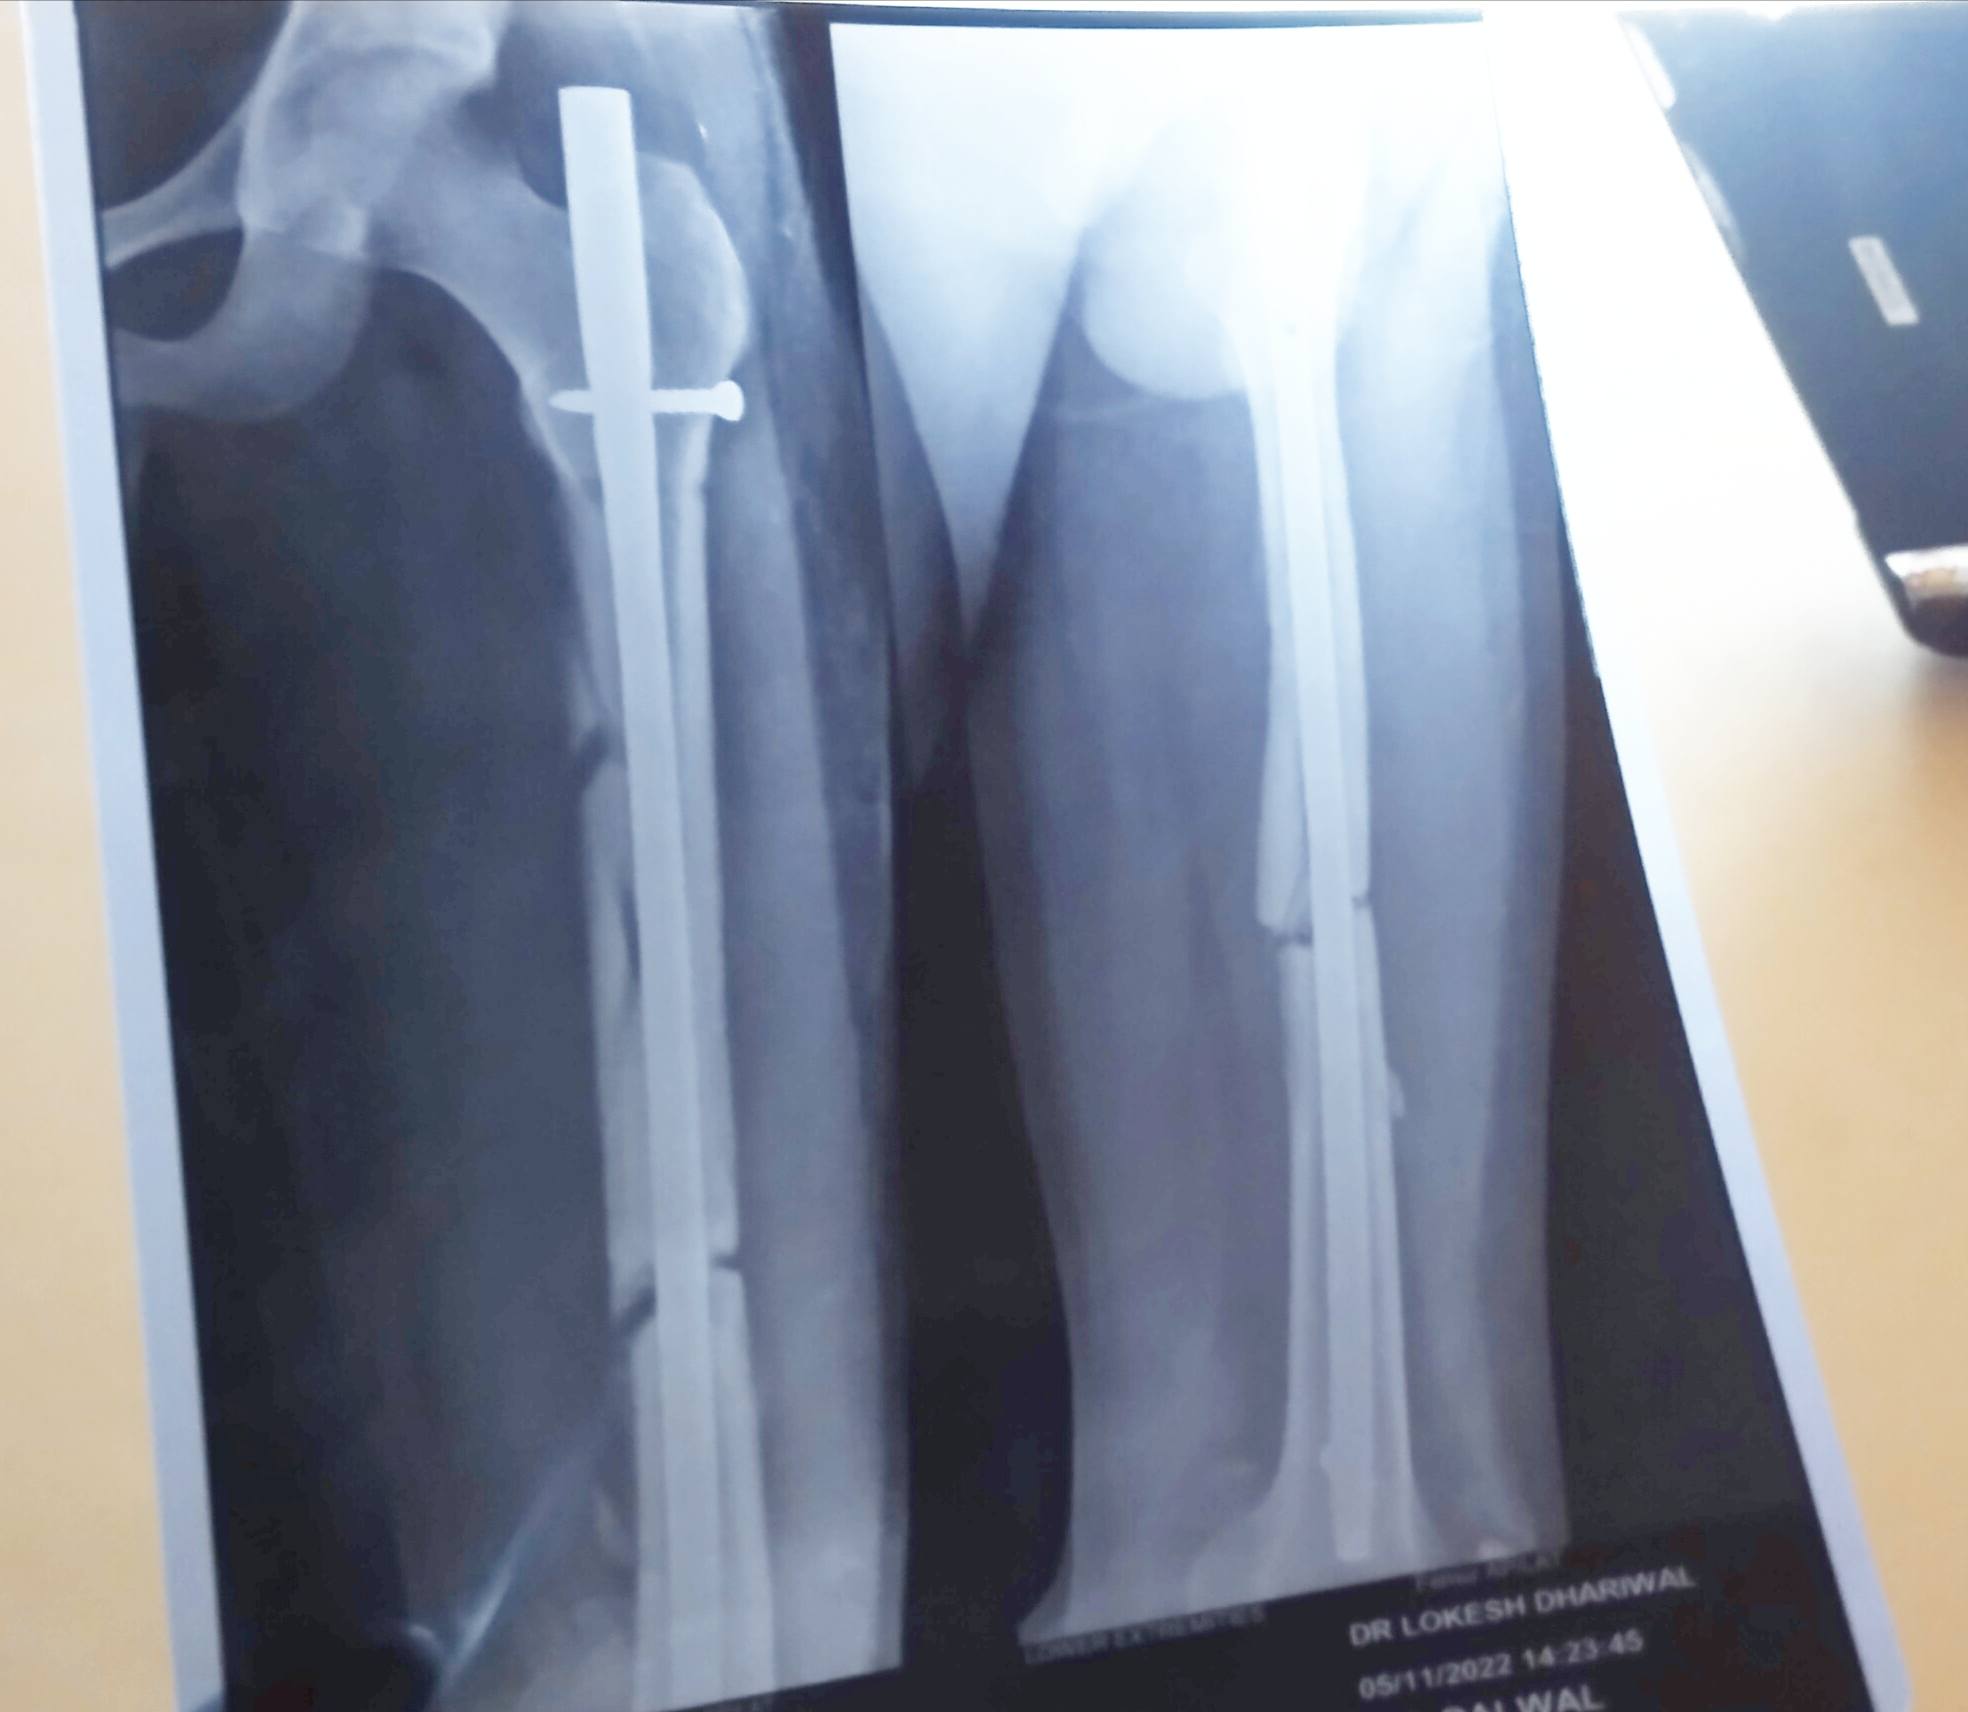

sir i wanna know that i haveno bone transformation in my x ray.Because when i done my first x ray after 1month of surgry but in second x ray which is done on 2month 25 day after surgery it hs not result.what should i hve to do mujhe abhi 3 mhinne hue hn femoral shaft displaced fracture tha

ye mere 2month 25 day bad ka h x ray